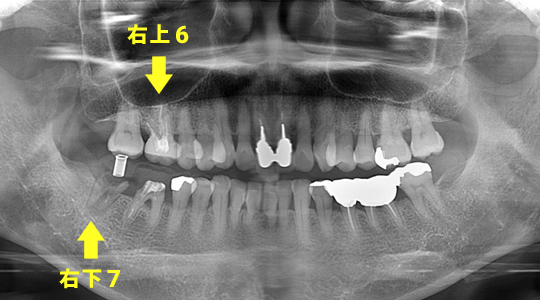

サイナスリフトによってかみ合わせが可能になるインプラント治療

エムドゲイン(歯周組織再生療法)と、CGF(あごの骨量を補う治療)を使用

<治療前>

右上6と右下7が駄目になっています

<CT画像での経過>

右上6と右下7にインプラントが埋入され咬み合わせができる状態。

義歯を応用したインプラント治療

<治療期間>

約1年3カ月